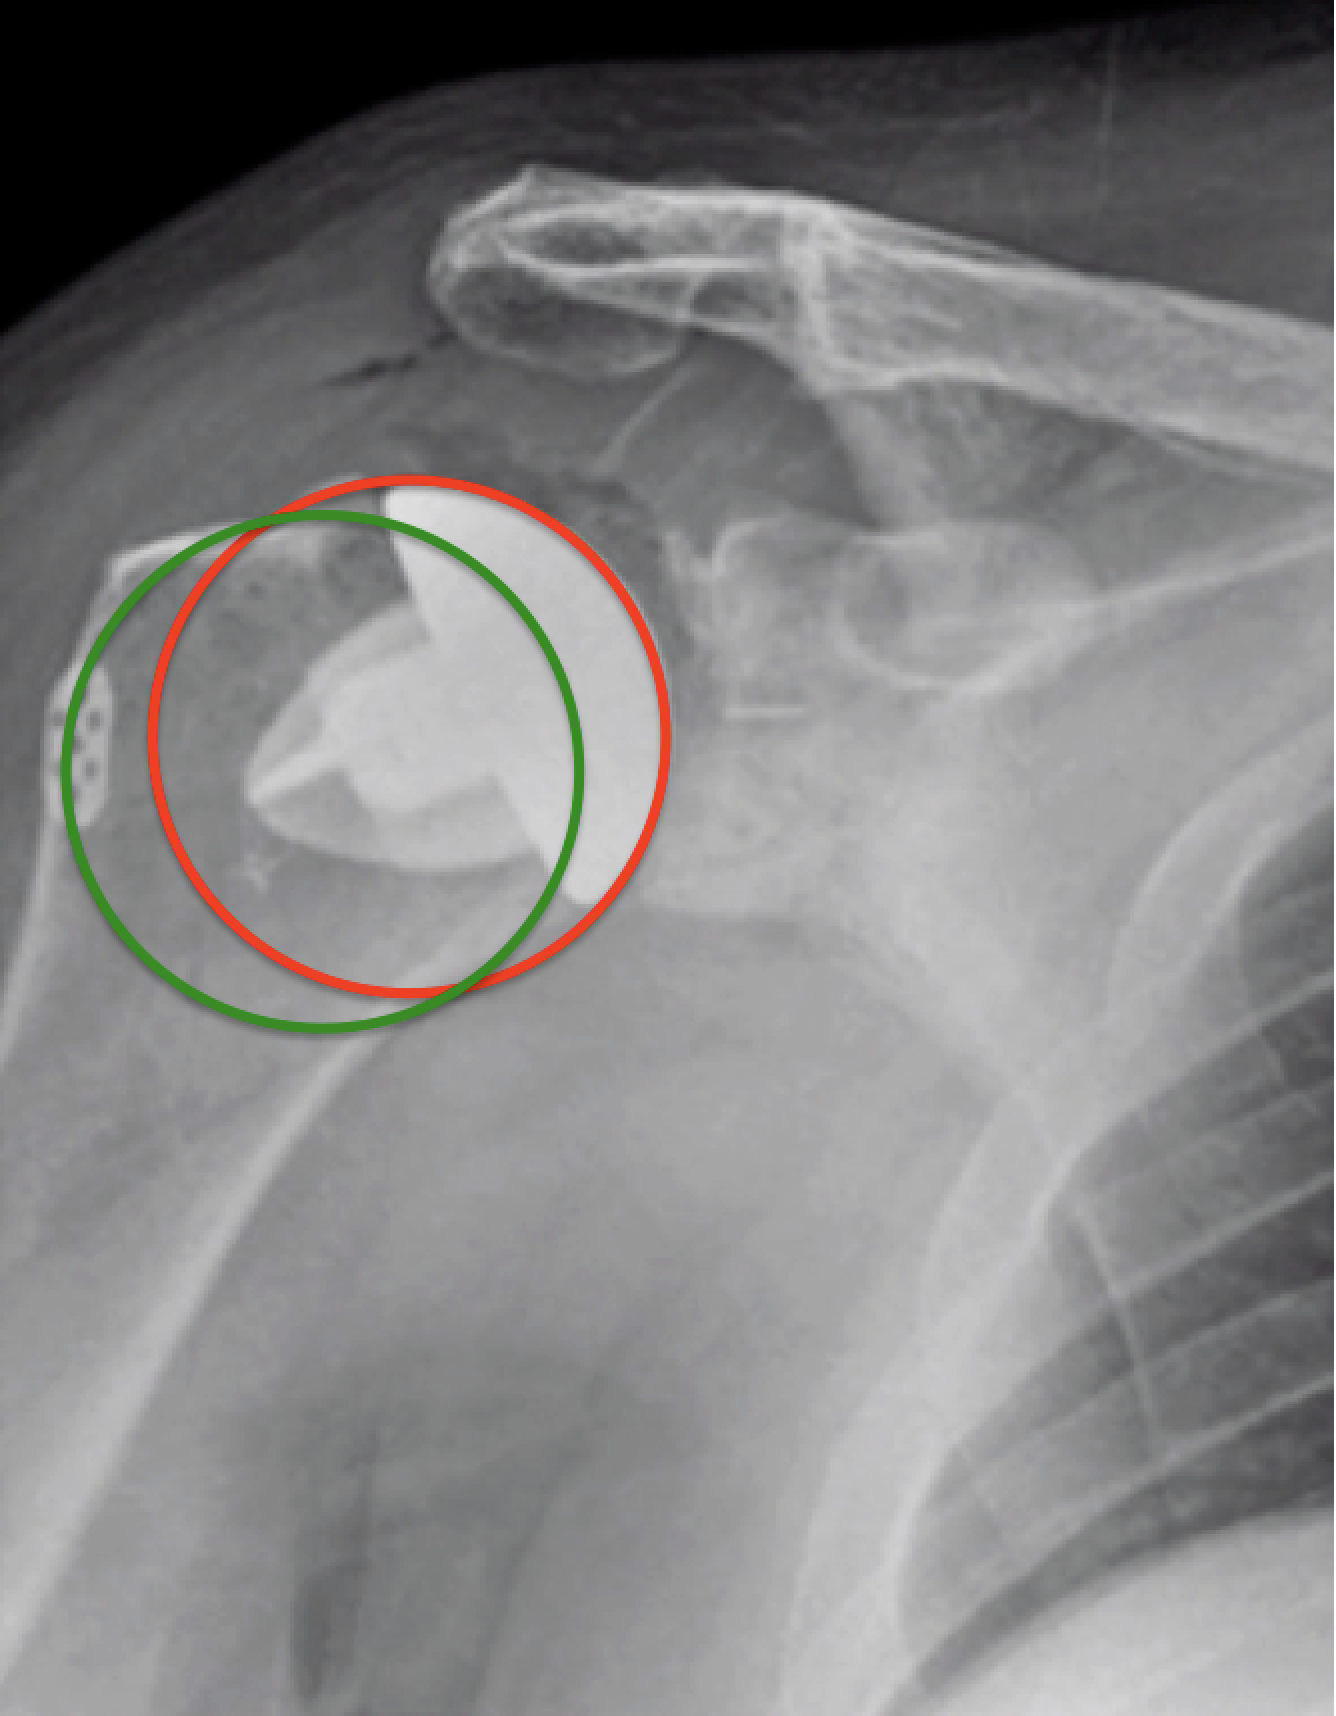

UW Shoulder and Elbow Academy Overstuffing and the importance of What Is The Right Humeral Head Again, let the name help you. Your humerus has a head (your proximal aspect, near your shoulder), shaft and distal aspect (the end at the bottom, near your elbow). The ridge toward the midline of the body, which you can see in the posterior view of the right humerus above, is called the medial supracondylar ridge. The shoulder joint, also. What Is The Right Humeral Head.

From faculty.washington.edu